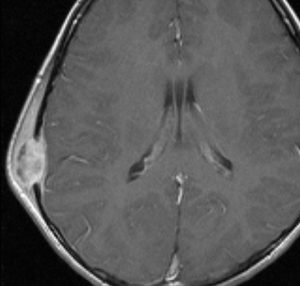

LCHの発生と自然退縮

51歳の男性にみられたものです。脳ドックをきっかけにみつかりました。何もないところから発生して増大してまた3ヶ月くらいで消失していきます。左上から1月間隔くらいのMRIです。

もちろん生検手術などしません。

ガドリニウム像です。極期を過ぎているのでリング状増強で,これも縮小消失していきます。